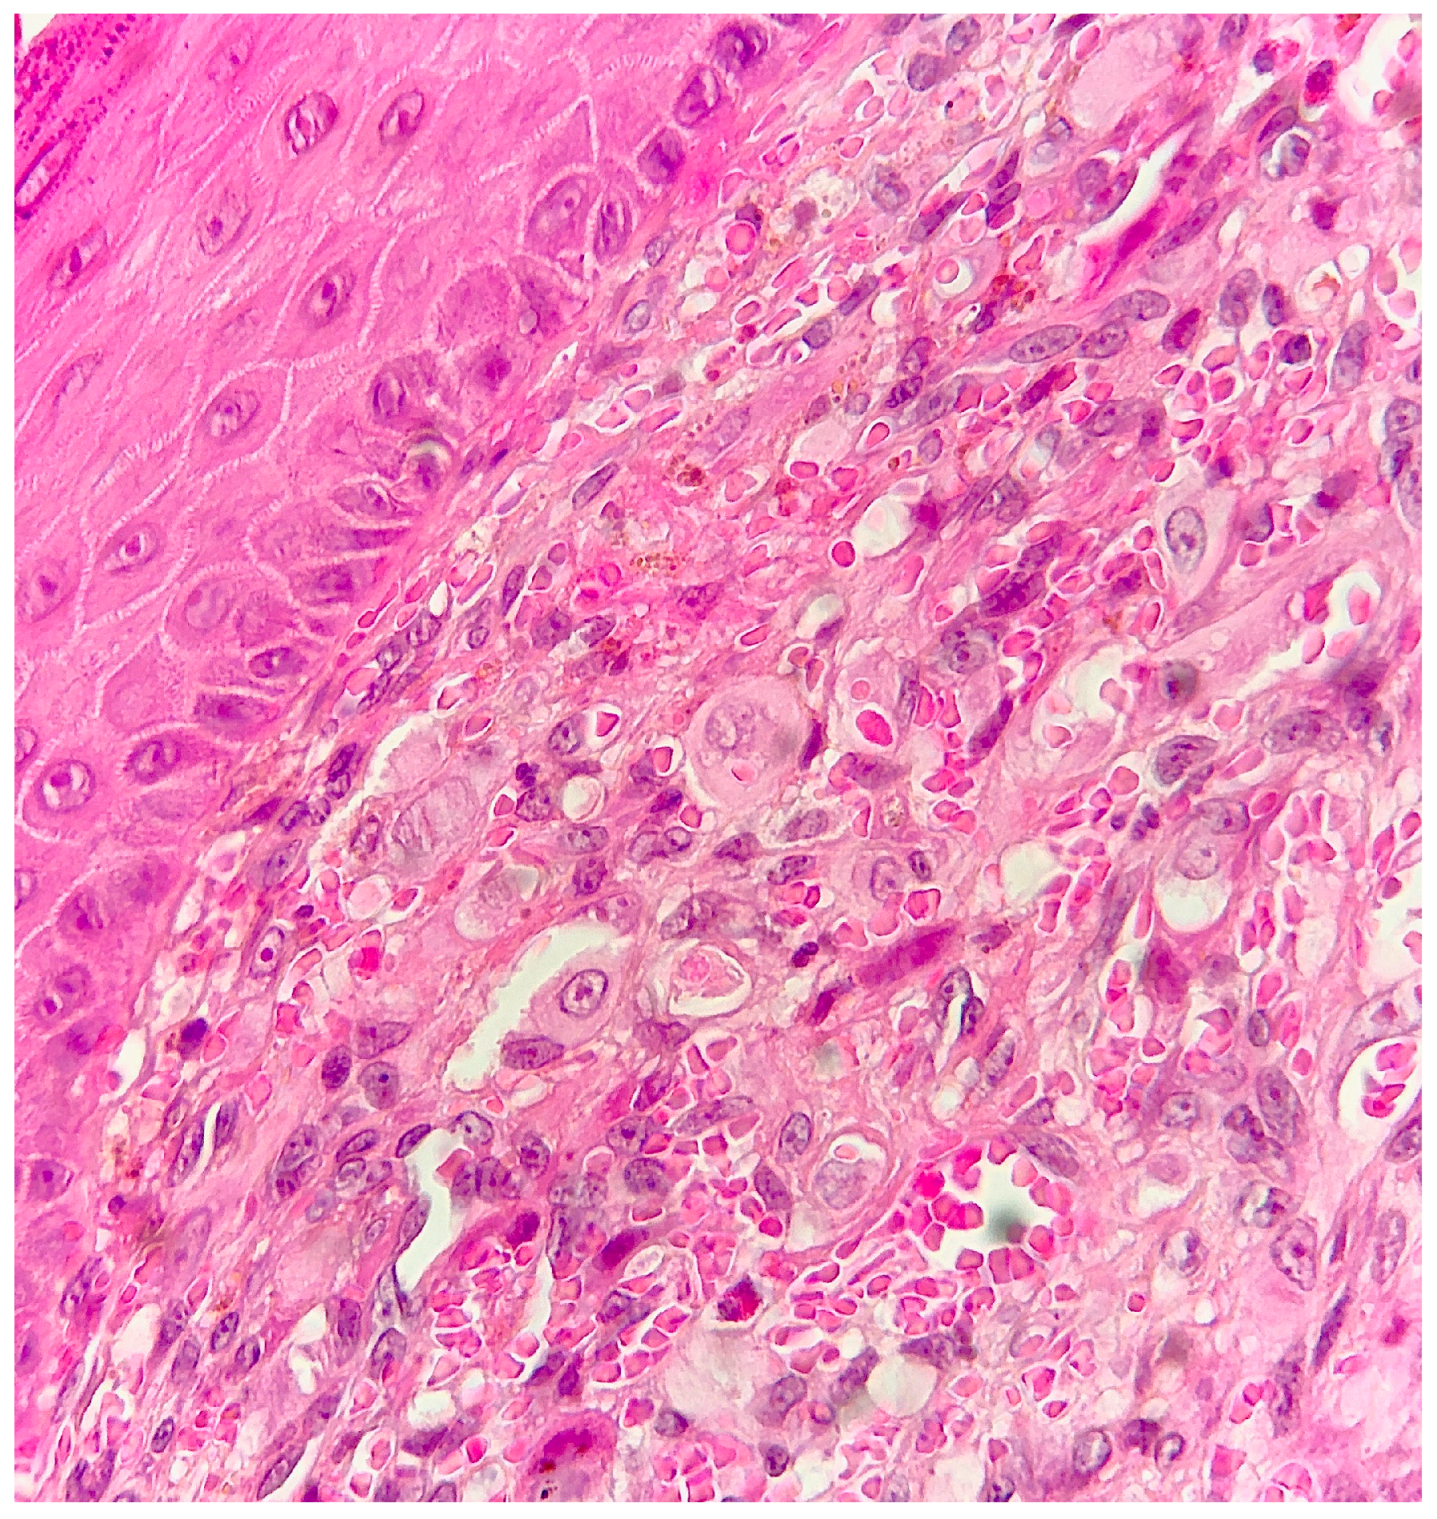

2. Case Report